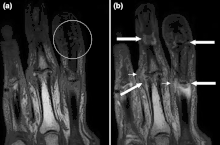

Magnetic resonance images of the fingers in psoriatic arthritis. Shown are T1 weighted axial (a) pre-contrast and (b) post-contrast images exhibiting dactylitis due to flexor tenosynovitis at the second finger with enhancement and thickening of the tendon sheath (large arrow). Synovitis is seen in the fourth proximal interphalangeal joint (small arrow). -